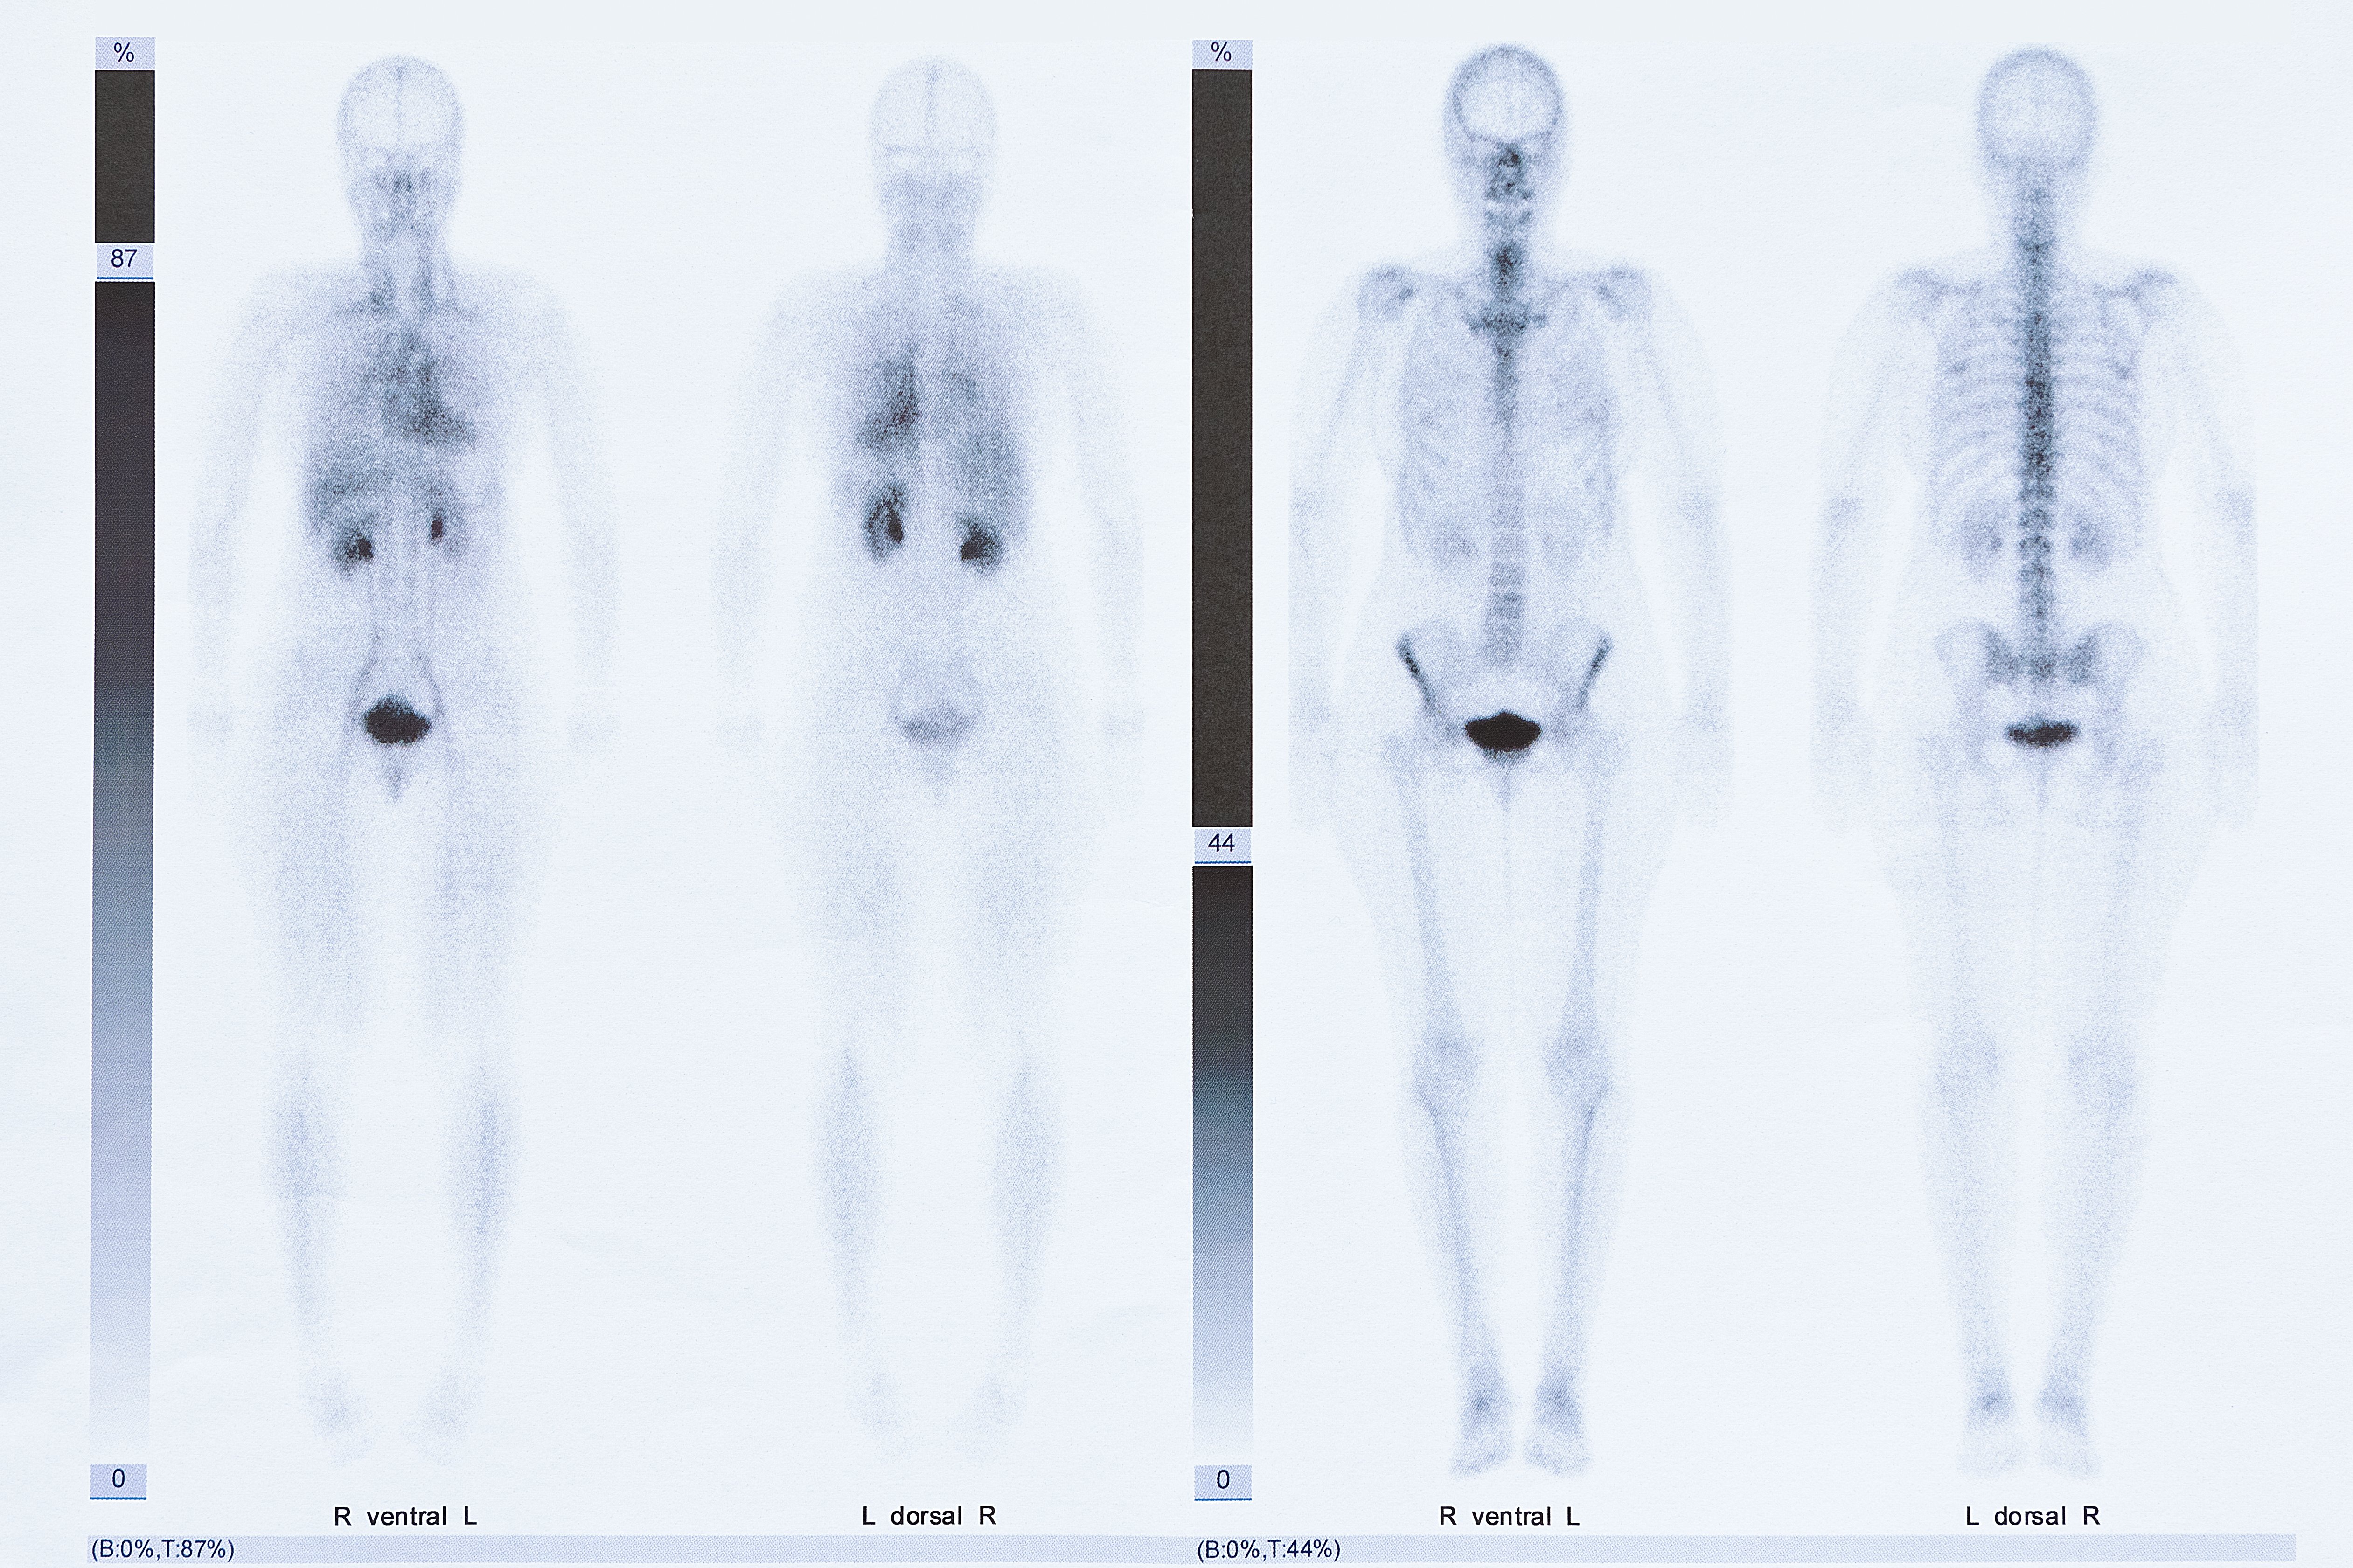

Symbolic image: Example of a scintigraphy

The generation of synthetic datasets using generative AI offers a promising solution to these challenges. By synthesizing medical imaging data, AI systems can be trained on a broader range of disease patterns without relying on rare or difficult-to-access patient data. This approach was pursued by a research team from the Division of Nuclear Medicine (Department of Biomedical Imaging and Image-guided Therapy) at MedUni Vienna, in a recently published study. A generative AI was trained on more than 9,000 scans from routine clinical examinations in the scintigraphy outpatient department. The model was then used to generate a synthetic image dataset that replicates the characteristic features of real medical imaging data but is entirely newly generated, ensuring that no patient-related information can be traced.